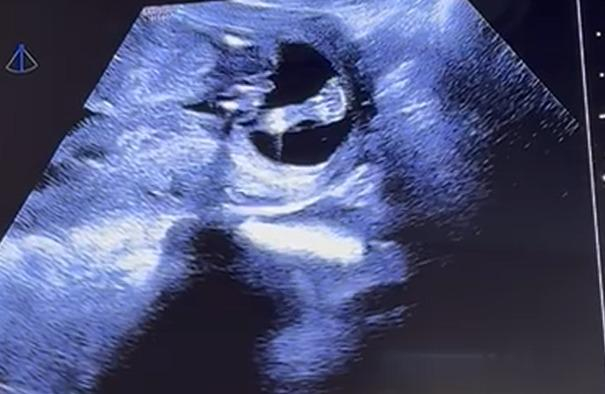

Guten Morgen,

ich bin derzeit in der 13. SSW und hatte letzte Woche einen Ultraschall. Was meint ihr, kann man das Geschlecht erkennen? Der Arzt hatte eine klare Tendenz die er uns leider bisher nicht mitgeteilt hat. Ich kann leider nichts wirklich erkennen. Hier die Bilder aus 12+3. Vielen Dank fürs Miträtseln.

@Memyslefandi Vielen Dank, dass du dir die Zeit genommen hast. Woran hast du es erkannt? Beim ersten Bild steht so viel ab, ich dachte sofort an einen Junge. Mein Mann wünscht sich so sehr einen Sohn

Ein Mädchen 🥰